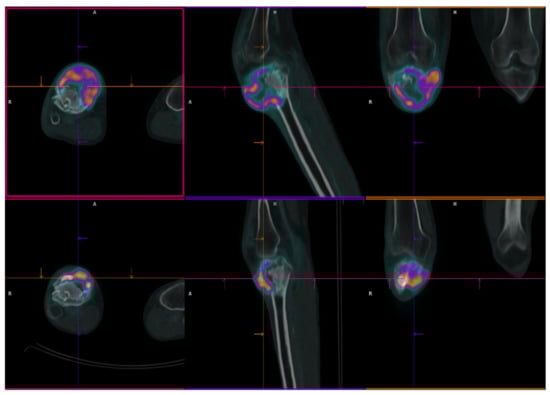

2.1. Patient 1

| Pt 1 | 29 | F | 0 | 17 July | Right femur | Curettage and bone grafts | 18 February | Neoadj denosumab (7 cycles) | 18 July Extraarticular resection: high-grade fibroblastic osteosarcoma | ISG/OS-2 | PD | I: IFO II: GEM.TXT III: PAZO | D 22 January | 9 | 53 | 43 |